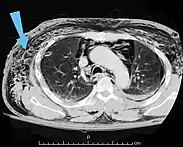

Scanner abdominal (rayons X) d'un patient présentant un emphysème sous-cutané (flèché) | |